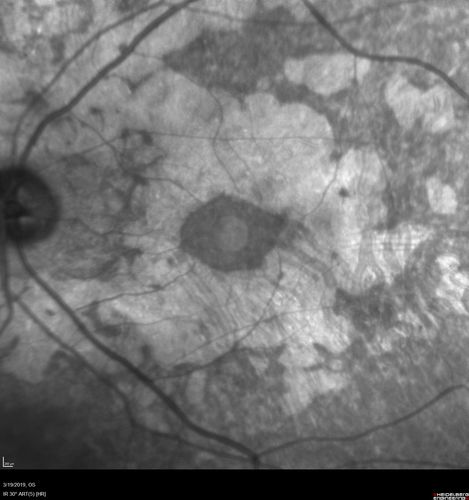

Concentric Geographic Atrophy

76 year old man Gradual vision loss

20/32 OD; 20/40 OS

No medicines, Non-smoker

Working and Driving